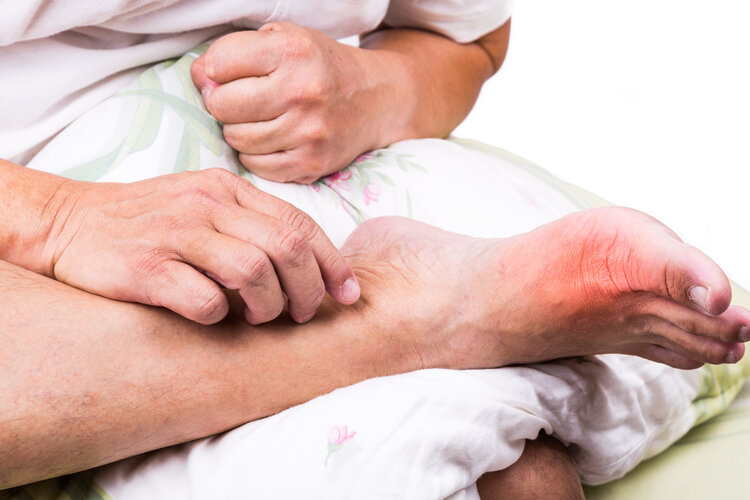

“太难受了!最大号的鞋子都穿不进去!”时值冬季 , 赵大爷穿着棉袄棉裤 , 脚上却耷拉着一双拖鞋 , 脚趾又红又肿 , 看上去特别瘆人 。

原来 , 赵大爷一直都有痛风的毛病 , 两年前右脚趾开始长痛风石 , 但却一直忍着 , 没有给予足够的重视 , 平时生活中犯疼时只靠止痛药熬过去 。 可有时候疾病就是这样 , 你越是不理 , 痛风石就越“猖狂” , 最终这“石头”不仅越来越大 , 还“跑”到别的地方折磨着赵大爷 。

如今 , 赵大爷脚上布满肿大的痛风石 , 皮肤被撑得越来越薄 , 赵大爷整日受疼痛折磨 , 大冬天也只能穿着拖鞋挨冻 , 要说不后悔也是假的 。

对患者而言 , 出现痛风石无疑是非常痛苦的 , 患者皮下可隆起大小不一的黄白色赘生物 , 破溃后还会流出脓性分泌物 , 痛感剧烈 , 严重影响到患者的肢体功能 , 影响行走 , 病情若持续发展还可能致残 。

此时如果不及时控制 , 尿酸盐沉积在关节 , 还会导致关节出现红、肿、热、痛等情况 , 关节表面皮肤也容易红紫、发亮 。